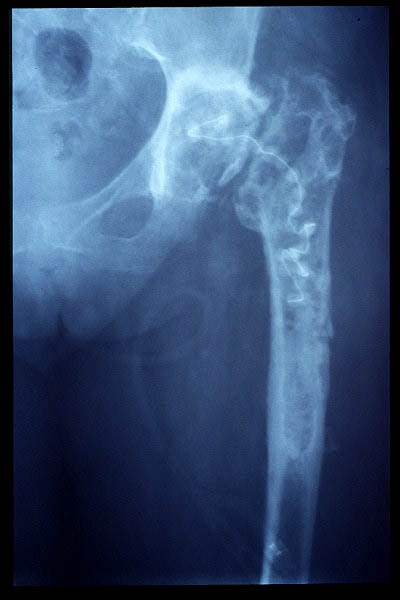

Fractura intertrocantérea de fémur, osteosíntesis